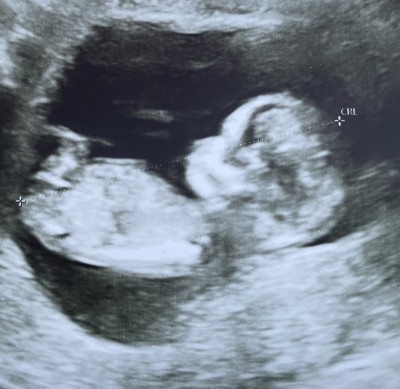

Kızlar 12+4deyiz. Ultrasona göre cinsiyet tahminleriniz olurmu.( Ne aceleniz var gidin doktordan öğreninciler cevap yazmasın. )Bizde biliyoruz ultrasonda gözükeceğini. Göstermedi cinsiyetini. Önemli olan sağlıklı olması tabiki heyecan ve merak… Deneyimli anneler tahminlerinizi bekliyorum :)

Gebelik haftası 12

KFa kemik yapısı kız bebek ile uyumlu bacak arası boş:)

Hayırlısı olsun canım ama kız bebiş